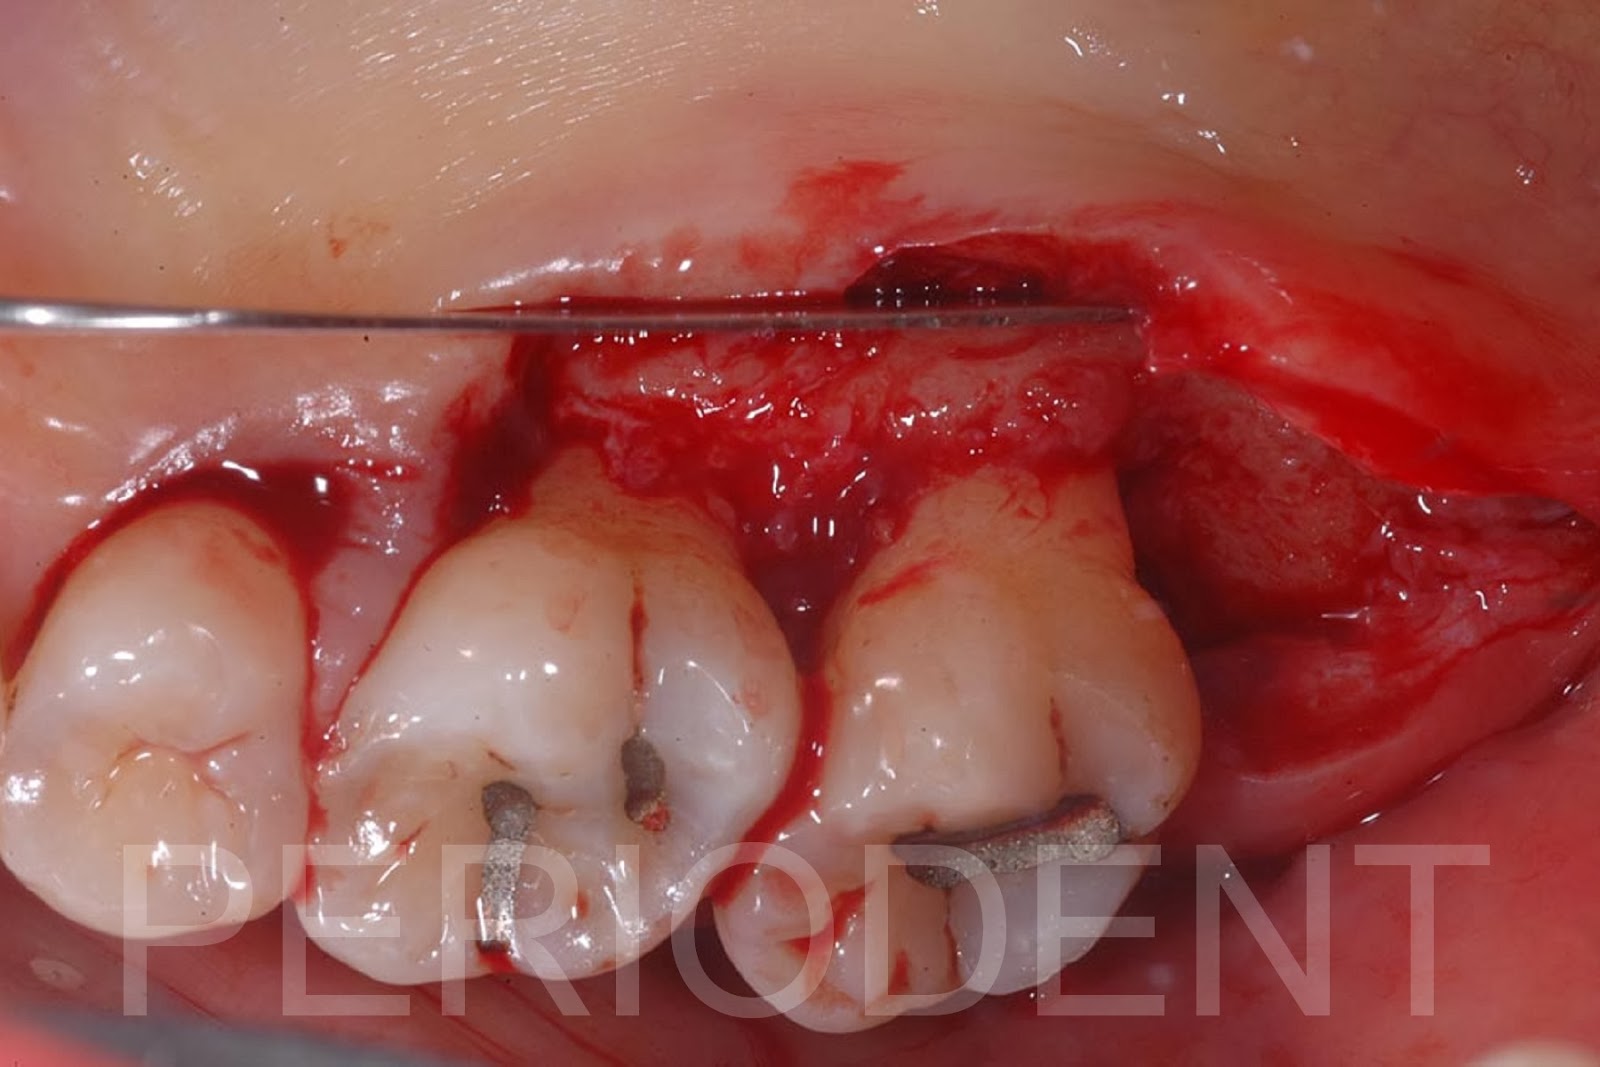

陳柏堅醫師發表上顎Distal Wedge手術之病例三